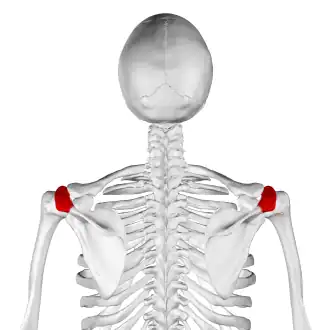

![]() Skeleton, posterior view. Acromion of each scapula shown in red. | |

Acromion

In human anatomy, the acromion (from Greek: akros, "highest", ōmos, "shoulder", pl.: acromia) or summit of the shoulder is a bony process on the scapula (shoulder blade). Together with the coracoid process, it extends laterally over the shoulder joint. The acromion is a continuation of the scapular spine, and hooks over anteriorly. It articulates with the clavicle (collar bone) to form the acromioclavicular joint.[1]